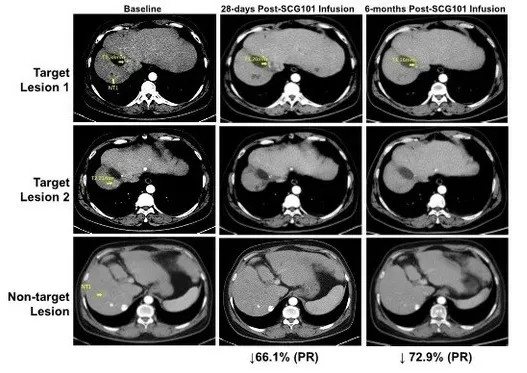

SCG101的突破性临床数据,已在2023年国际细胞与基因治疗大会(ISCT)上公布,本例乙型肝炎病毒(HBV)相关肝细胞癌(HCC)患者,在接受SCG101单药治疗后,肿瘤及HBV感染均得到缓解。

1、肿瘤改善:该患者在治疗第28天,获得部分缓解(PR),肿瘤靶病灶缩小66%(相比基线);并且在治疗第4个月时,进一步缩小74.5%;而另一处病灶则完全消失。截至数据统计时,该患者处于持续缓解状态,肿瘤未进展时间已超过6.9个月!

图2 HBV相关HCC患者回输SCG101前后的影像学变化

▲图源“CISION”,版权归原作者所有,如无意中侵犯了知识产权,请联系我们删除